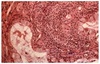

A 34 year-old male presents to you for evaluation of persistent right-sided tinnitus for 6 months. Examination of the ears is unremarkable. Audiologic testing reveals a unilateral normal sloping to moderate high frequency sensorineural hearing loss. MRI of the brainstem reveals a right cerebellopontine (CPA) lesion with evidence of growth compared to prior scans. The patient undergoes excision of this lesion with tissue analysis revealing the histiology shown. Which of the following is true regarding this patient’s diagnosis?

A. This tumor comprises approximately 50% of CPA tumors

B. High-resolution, contrast-enhanced MRI would reveal intermediate signla wiht marked enhancement with gadolinium with evidence of a dural tail

C. Hitselberger’s sign is the most common presenting symptom

D. CT-scan would likely show bony erosion and destruction of middle ear structure

E. None of the above